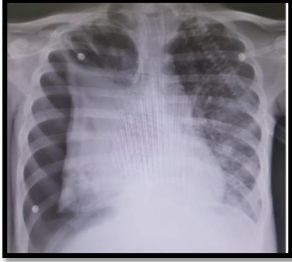

Analise a radiografia abaixo e responda

Fonte: acervo do autor

Assinale a alternativa que apresenta o tratamento imediato que deve ser proposto para este caso.